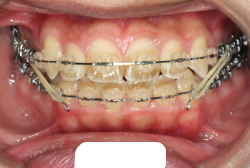

診断の結果、典型的なアングル2級1類の上顎前突です。上下歯列の正中の不一致も見られます。しかし、歯の大きさは平均値に近く、配列の凸凹がそれほど見られません。このまま放置すると、将来的には抜歯を伴う矯正治療を行う可能性が高くなりますが、このタイミングで適切な治療をすると、非抜歯治療が可能かもしれません。

矯正歯科医が着目するのは、奥歯の噛み合わせの位置関係です。前歯の位置にそれなりの差が生じていても、奥歯の位置が正しければそれほど重症という評価にはなりません。このケースの場合は、上下の第一大臼歯の位置関係は、直線的に一致しているタイプでした(矢印が一致)。混合歯列時期の奥歯の位置関係としては、ほぼ正常な状態といえますが、症状から言うと、上の奥歯をもっと後ろに下げてやることができれば、上顎歯列全体に余裕ができるので、凸凹も解消できるし、前歯の傾きを内向きに修正することもできると考えられました。しかしこのまま全体に永久歯が生えきってしまうと、上の前歯が出たままになってしまいますので、生え替わりが完了する前に大急ぎで奥歯を後ろに下げる必要があると判断しました。

こういう症状でもっとも効果があるのが、顎外固定装置と言って、お口の外部から奥歯に力をかける方法です。 写真の装置はネックバンドというタイプの装置です。この装置は取り外し式ですので、夜寝るときに毎日自分で取り付けて、寝ている間に少しずつ上の奥歯を後ろに下げていきます。この装置には、奥歯を後ろに下げる効果だけでなく、上顎の過剰な成長発育の抑制、下顎の成長促進作用があるとされており、上顎前突の症状にはいずれも有利な効果が期待できます。

ネックバンドを1年半使用して、上顎大臼歯が十分後ろに下がったところで、裏側にリンガルアーチという固定のワイヤーを取り付けて、新しく生じた隙間が狭くならないよう「保隙(ほげき)」という処置をして、永久歯が生えそろうまで待機中の様子です。配列全体に隙間が生じているのがお分かりいただけると思います。これだけの隙間が確保できていれば、抜歯をしなくても、あとで上の前歯を内側に理想的な角度で引っ込めることができます。このように完全に永久歯列になる前に、十分な隙間が確保できるかどうかが、非抜歯で矯正できるかどうかの分かれ目になります。

初診時と違い、上の奥歯がより後方に下がっていることが分かります。ただしこの段階では奥歯は後ろに下がりすぎの状態です。しかし次の段階でマルチブラケット法を始めると、上の奥歯は次第に前にズレて来ます。最終段階で正しい位置にするためには、この段階では余分に後ろに下がっている必要があります。

第2段階としてマルチブラケット法を非抜歯で1年間行いました。歯の傾斜が修正され、正中も一致し、美しく機能的な配列に仕上がりました。再診時に確保した隙間をすべて使って、すべての永久歯を理想的な位置に配列することができました。前傾していた上の前歯は真っ直ぐに直立し、完全な正常咬合が確立できています。